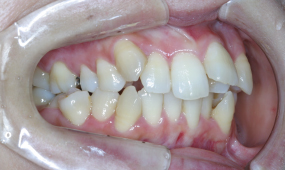

| 口腔内所見 | 歯のサイズと顎の骨の大きさの不調和が著しく上下とも叢生(歯のガタガタ)量が大きく、奥歯の噛み合わせは上の歯が前にずれていて出っ歯の状態となっていました。上下の歯の真ん中は約4mmずれており、また舌小帯(舌の裏のスジ)が短く、舌の動き(噛んで飲み込む動作や発音)を制限していました。口唇や頬は伸展性が乏しく、その力により口腔容積は著しく小さくなっている傾向にありました。 |

| 診断名 | 著しい叢生(歯並びのガタガタ)を伴う上顎前突症例 |

| 装置名 | リンガルブラケット矯正装置(上顎)、マルチブラケット装置(下顎)、歯科矯正用アンカースクリュー |

| 抜歯部位 | 上下左右4番、上顎左右7番抜歯 |

リンガルブラケット矯正装置(歯の裏側からの装置)、下は表からのマルチブラケット装置を希望。著しい叢生(ガタガタの歯並び)に対して上下左右計4本の抜歯で排列と前歯の後退を図りました奥歯の噛み合わせのズレに対しては上顎左右第二大臼歯(12歳臼歯)を抜歯し、上顎歯列全体を遠心(後方)移動させることにより正常な噛み合わせの位置を獲得します。

■リンガルブラケット矯正装置の使用

舌側矯正では叢生(歯並びのガタガタ)が強いと装置が着かず、隣り合う装置同士の距離が狭くなり歯を並べるのに時間と労力がかかります。

■奥歯の抜歯、歯の移動による噛み合わせの改善

また骨格的なずれと歯の並びの前後的ずれがあるケースでは、奥歯の抜歯を要する場合があり、歯の移動やコントロールが難しくなります。このケースはまさに難易度特大で4年以上の治療期間がかかりましたが、患者さんの協力と歯科矯正用アンカースクリューに助けられ、うまく目標を達成できたケースでした。患者さんも仕上がりにはかなり満足していただいています。